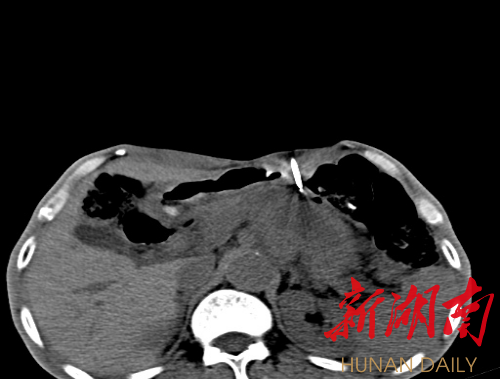

新湖南客户端2月16日讯(通讯员 刘强)近日,湘西土家族苗族自治州人民医院CT室微创介入团队成功为一名胰腺占位患者实施了CT引导下胰腺穿刺活检术,经病理检查确诊为胰腺癌。该术式的成功开展标志着该院在腹部肿瘤诊断方面取得一大突破,CT介入技术用于肿瘤诊断再上一个新台阶。

经过术前为患者做好胃肠准备以及局麻后,在CT精准引导下,主任医师邓宏将套管针经皮穿刺,经多次方向调整,快速经过胃前后壁,成功达到胰腺肿块内,医生瞿枫穿入活检针后快速精准取样,顺利完成了这台高难度的穿刺活检术。手术总时长不到20分钟,患者术中及术后无其它不适。经过术后禁食24小时,一个星期后观察没有并发症发生,样本经病理科固定、切片、染色与显微镜,最终诊断为胰腺癌。